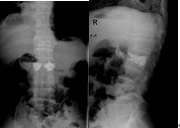

微创骨科采用经皮椎体成形术治愈了89岁老奶奶腰椎骨折(微创骨科:任杰)

刘奶奶,89岁,因上厕所摔伤腰痛,翻身困难,不敢坐起和下地行走,疼痛难忍4天,卧床没有好转,来我院微创骨科就诊,经检查腰椎3压痛、叩痛,拍x光片和核磁确诊腰椎3骨折。因骨质增生腰椎麻醉困难,微创骨科任杰主任应 用最先进的微创技术采用局麻下行椎体成形术,术后老人家就感觉疼痛马上减轻了,儿孙都非常高兴,老人不用卧床了,可以下地行走自己上厕所、坐着吃饭。避免了保守治疗需卧床3个月引起的并发症:坠积性肺炎、褥疮、下肢静脉血栓、严重骨质疏松、泌尿系感染和结石等,甚至危及生命。家人感激不尽,老人不用卧床遭罪了,减轻了家人护理负担,不用耽误工作,保证老人正常生活质量,延长了寿命。

随着老龄化社会的到来,骨质疏松性骨折发病率逐年增加。近年来针对骨质疏松性椎体骨折因不能采取有效内固定,而采用了椎体成形术。微创手术—经皮椎体成形术(PercutaneousVertebroplasty,PVP)是指经皮通过椎弓根或椎弓根外向椎体内注入骨水泥以达到增加椎体强度和稳定性,防止塌陷,缓解疼痛,甚至部分恢复椎体高度为目的一种微创脊椎外科技术。

术前

术后